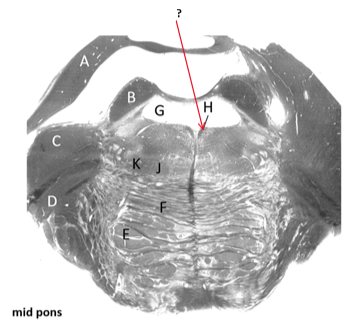

Name this and state its pathway.

Fourth ventricle.

Third ventricle–>4th ventricle–> subarachnoid space.